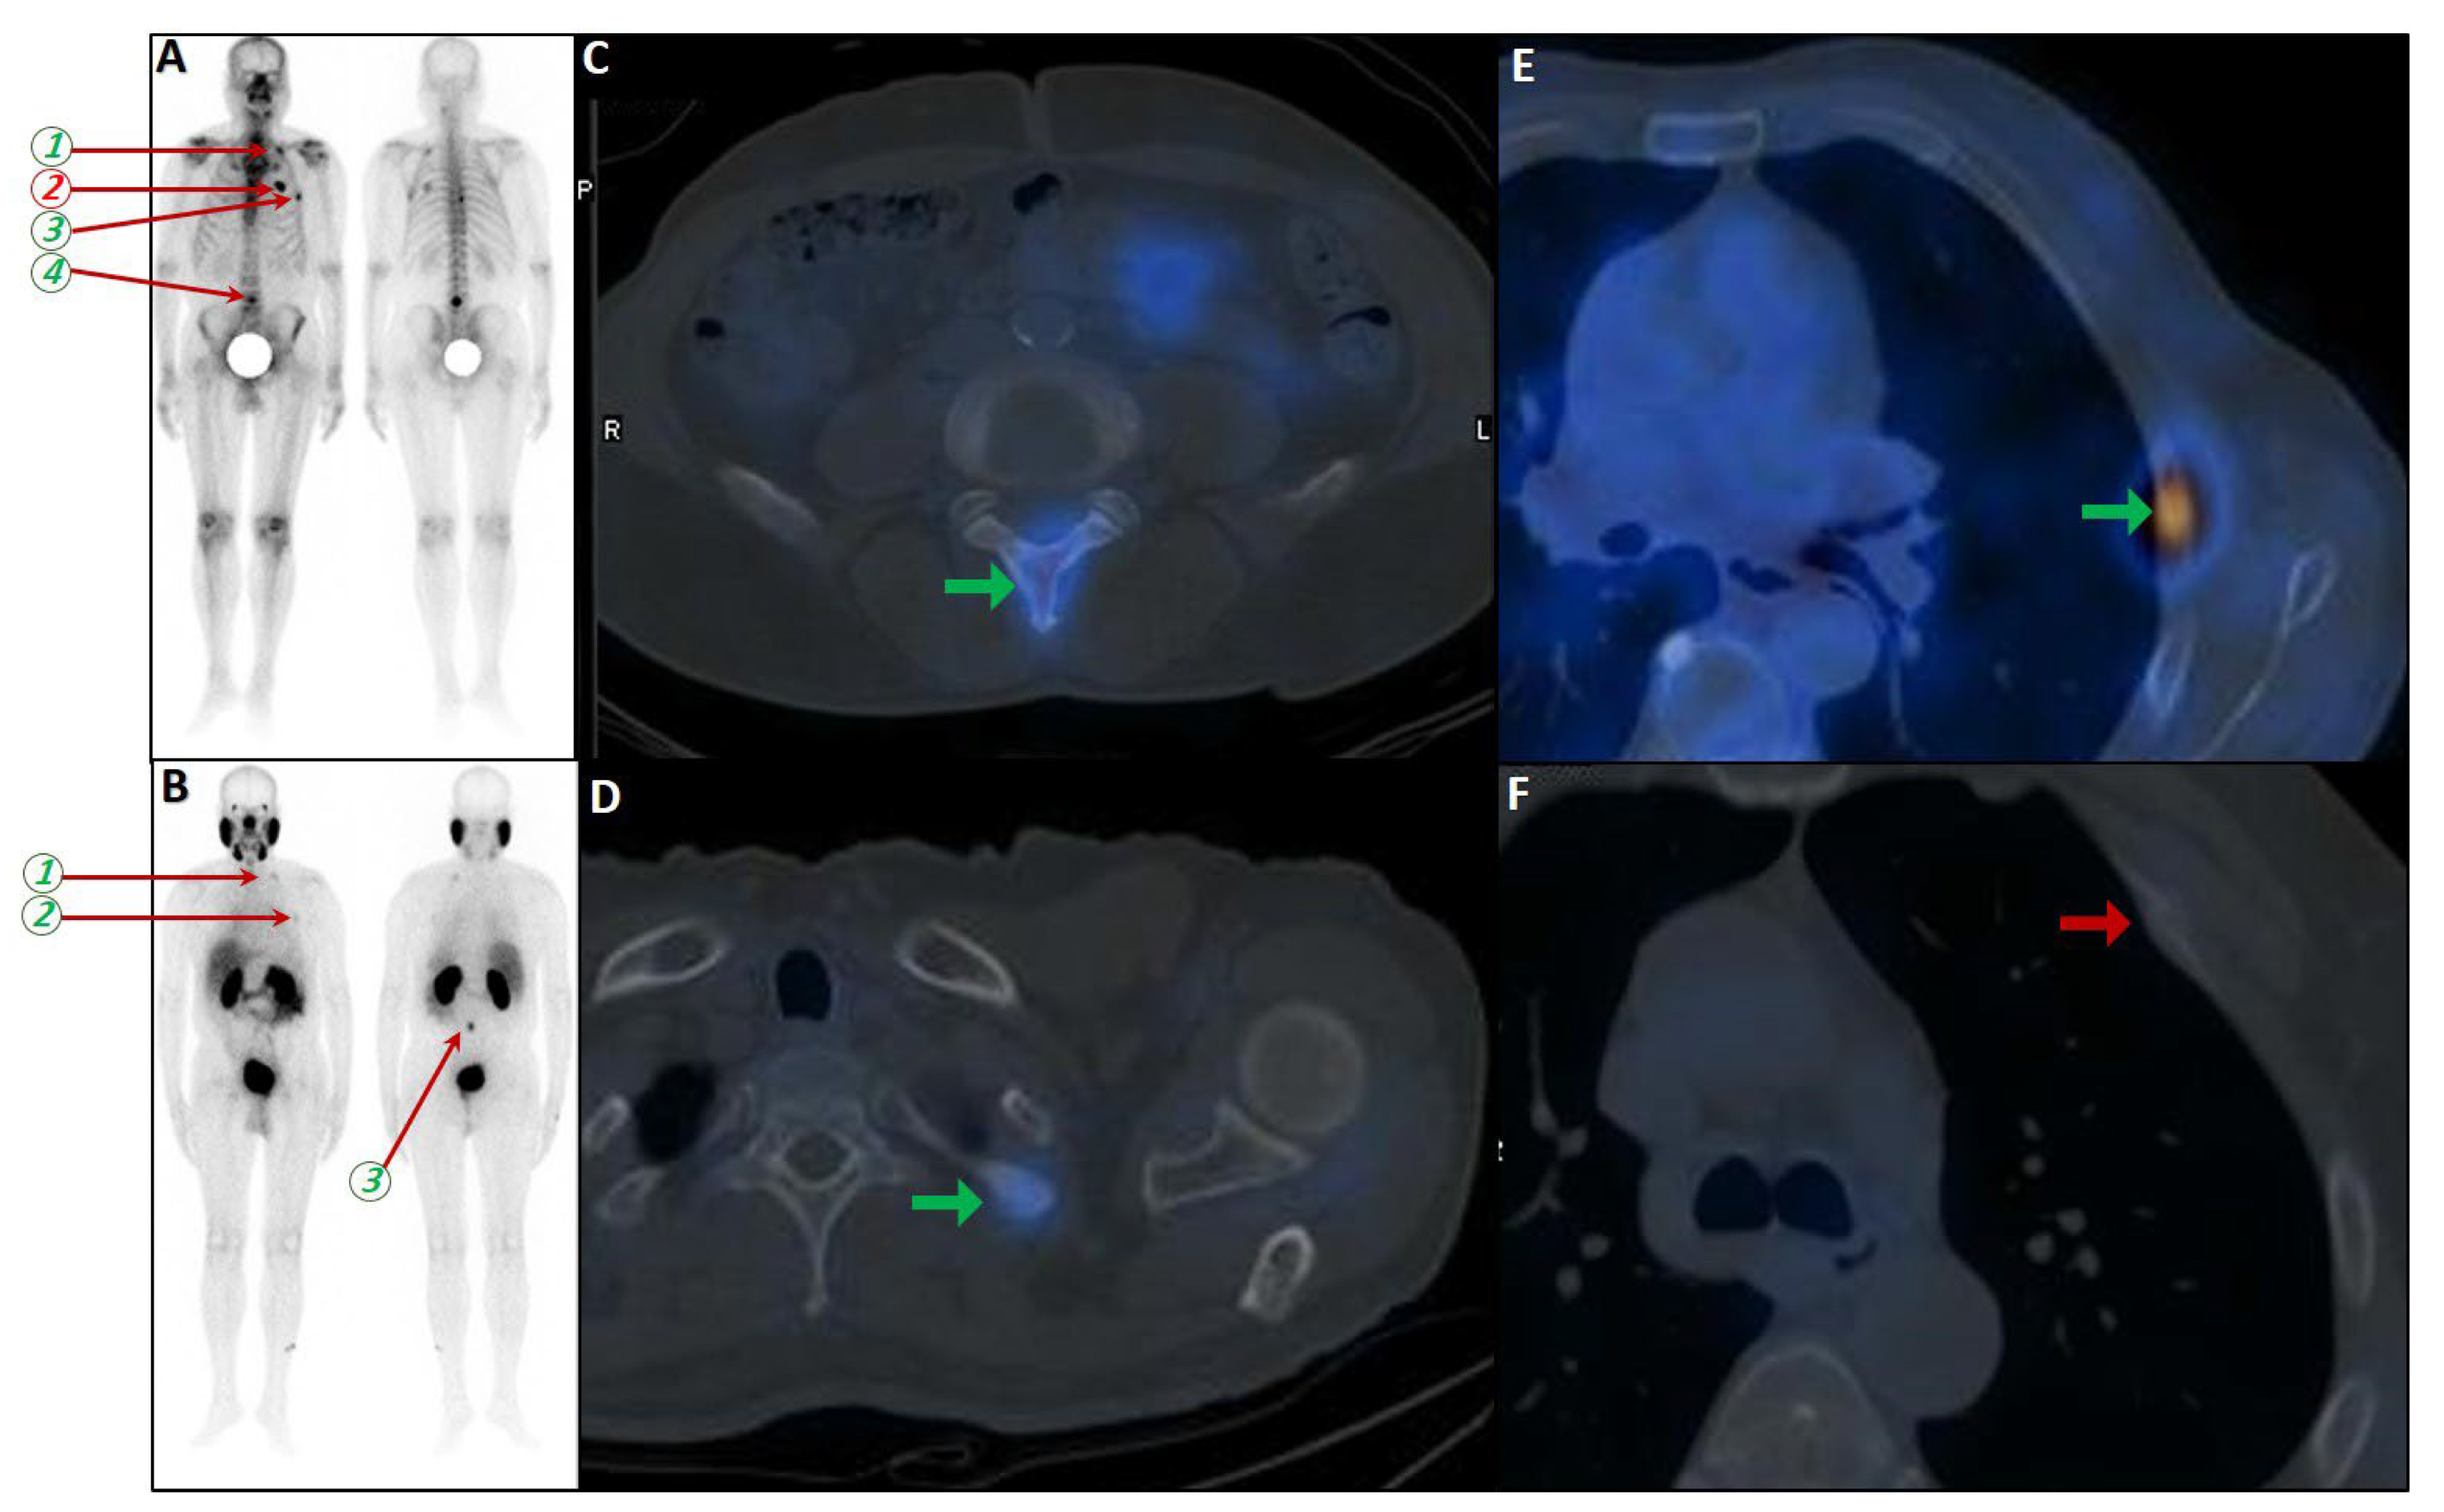

- Benecke, J.A.; Calderón, E.; Reischl, G.; Brendlin, A.; Tsaur, I.; la Fougère, C.; Vogel, J. Focal Unspecific Bone Uptake on [18F]PSMA-1007 PET: Evaluation Analog PROMISE Criteria and Validation via PET/CT Follow-Up. Diagnostics 2024, 14, 2327. [Google Scholar] [CrossRef]

- Bauckneht, M.; D’Amico, F.; Albano, D.; Balma, M.; Cabrini, C.; Dondi, F.; Di Raimondo, T.; Liberini, V.; Sofia, L.; Peano, S.; et al. Composite Prediction Score to Interpret Bone Focal Uptake in Hormone-Sensitive Prostate Cancer Patients Imaged with [18F]PSMA-1007 PET/CT. J. Nucl. Med. 2024, 65, 1577–1583. [Google Scholar] [CrossRef]

- Seifert, R.; Telli, T.; Opitz, M.; Barbato, F.; Berliner, C.; Nader, M.; Umutlu, L.; Stuschke, M.; Hadaschik, B.; Herrmann, K.; et al. Unspecific 18F-PSMA-1007 Bone Uptake Evaluated Through PSMA-11 PET, Bone Scanning, and MRI Triple Validation in Patients with Biochemical Recurrence of Prostate Cancer. J. Nucl. Med. 2023, 64, 738–743. [Google Scholar] [CrossRef]

- Yin, Y.; Werner, R.A.; Higuchi, T.; Lapa, C.; Pienta, K.J.; Pomper, M.G.; Gorin, M.A.; Rowe, S.P. Follow-up of Lesions with Equivocal Radiotracer Uptake on PSMA-Targeted PET in Patients with Prostate Cancer: Predictive Values of the PSMA-RADS-3A and PSMA-RADS-3B Categories. J. Nucl. Med. 2019, 60, 511–516. [Google Scholar] [CrossRef] [PubMed]